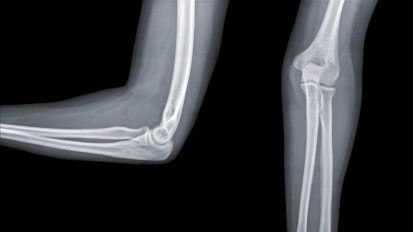

Terrible Triad Injuries and the Complex Elbow: Anatomy and Biomechanics Video

Terrible Triad Injuries and the Complex Elbow: Anatomy and Biomechanics

Neil S. Tarabadkar, MD, discusses elbow dislocations, historical analysis, current concepts and diagnostics surrounding the topic of triad injuries.